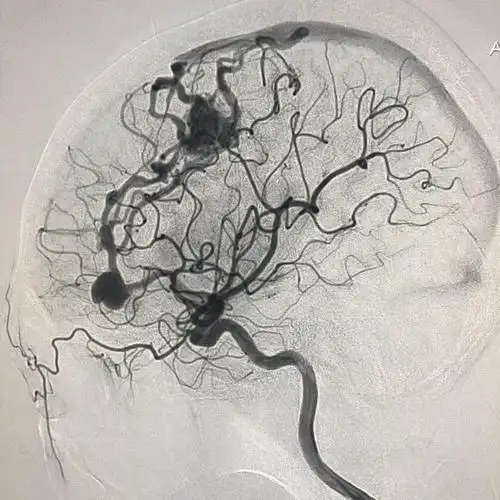

王雪梅,女,44,左侧脑血管畸形动脉瘤